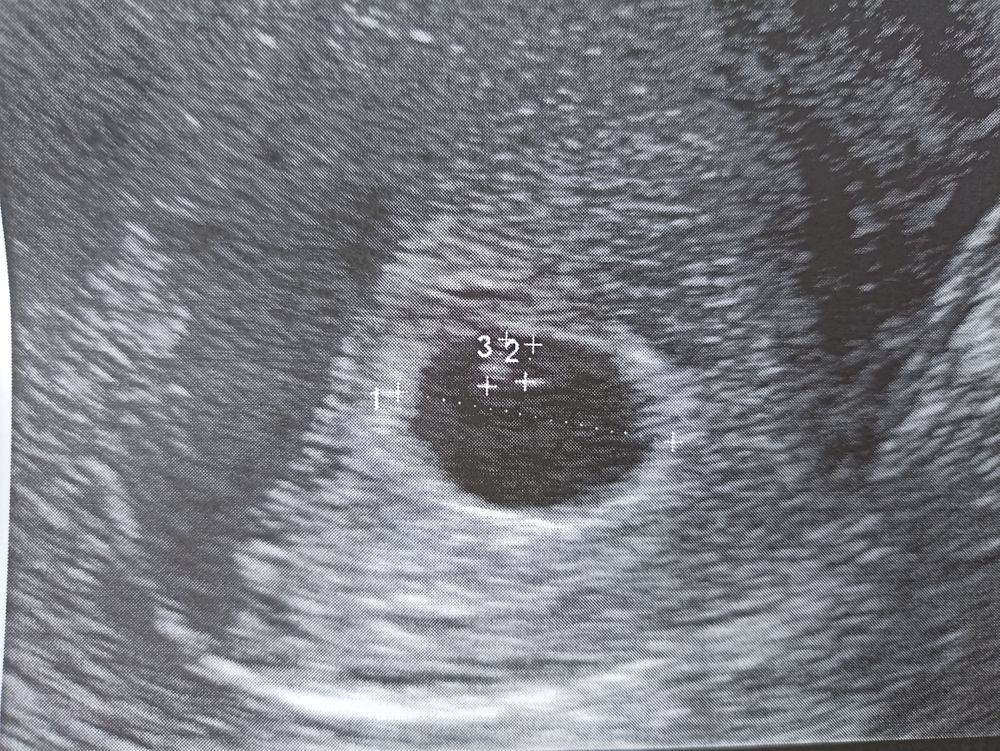

Первый цикл после зб и чистки. Вчера на 24 ДЦ первый положительный тест на О. 1 вчера днем, 2 вчера вечером и 3 сегодня. Немного светлеет. По идее О сегодня, но ничего не чувствую совсем.